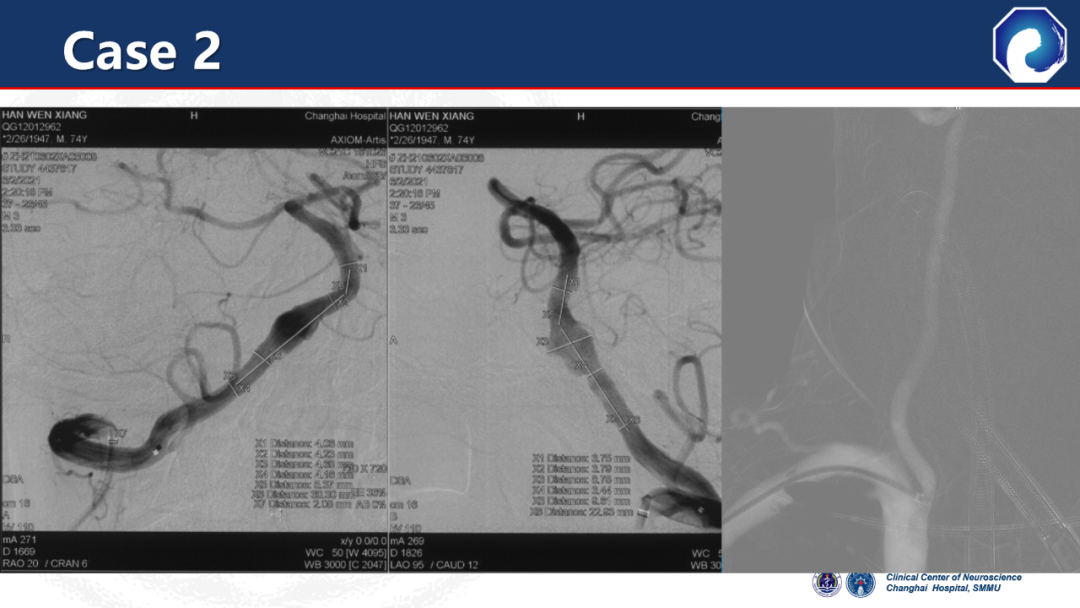

CASE 2

桡动脉释放血流导向装置,椎动脉和锁骨下动脉成角明显;通桥医疗银蛇®DA顺利到达V3段,提供稳定支撑;顺利释放血流导向装置,导管头端无移位。